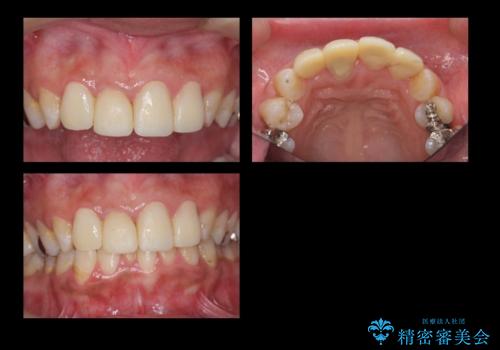

- 前歯の被せもののやり直しを希望して来院。

隣の歯もつぎはぎでプラスチックが劣化していたため、虫歯を取りセラミックでかぶせました。

保険治療の前歯の被せものの縁(マージン)が歯茎の中まで及んでいたため、歯周外科手術を行い、マージンが歯肉縁下深くならないように設定しました。

右上1番は、根の治療のやり直しをしています。